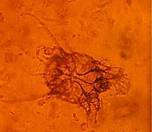

Mange mites

May be few clinical signs, but the piglet can act as a host to the mite and must be included in any eradication programme